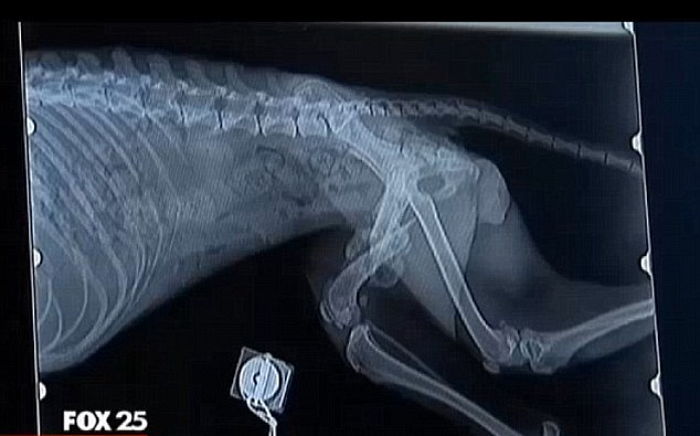

동물병원으로 이송된 강아지를 진찰한 수의사 마타 스미스 블랙모어(Martha Smith-Blackmore)는 경악을 금치 못하기도 했다.

수의사는 “누군가 칼로 강아지 혀를 고의로 자르고 눈을 찔렀다. 평균보다 무게가 절반도 채 나가지 않는 굶주린 강아지는 여러 차례 불로 학대당한 흔적이 명백하게 남아있었다”고 말했다.

야구방망이 같은 단단한 물건에 맞아 척추까지 뼈가 모두 골절돼 걷지도 못하는 상태였던 강아지는 숨을 쉬고 있는 자체가 고통스러운 상태였다.